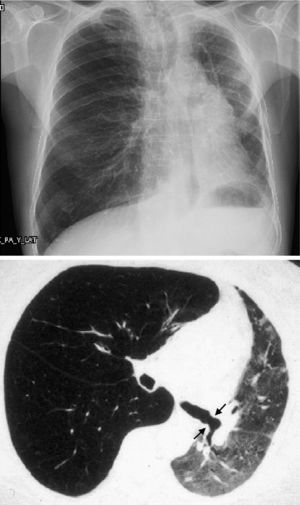

When the underlying disease is emphysema, the residual native lung tends to distend and herniate into the contralateral hemithorax, causing partial collapse of the graft (Fig. 2). Progressive air trapping produces hyperinflation in the native lung, but this does not usually present problems when the lung is functioning adequately. On occasions, the progressive distention of an emphysematous lung may compromise graft function, so volume-reducing surgery on the native lung may be necessary. Interference from an emphysematous lung may mean that functional improvement in these recipients is poorer than in those with interstitial disease. Improvement is also seen in pulmonary volumes, DLCO, gas exchange and exercise capacity.9